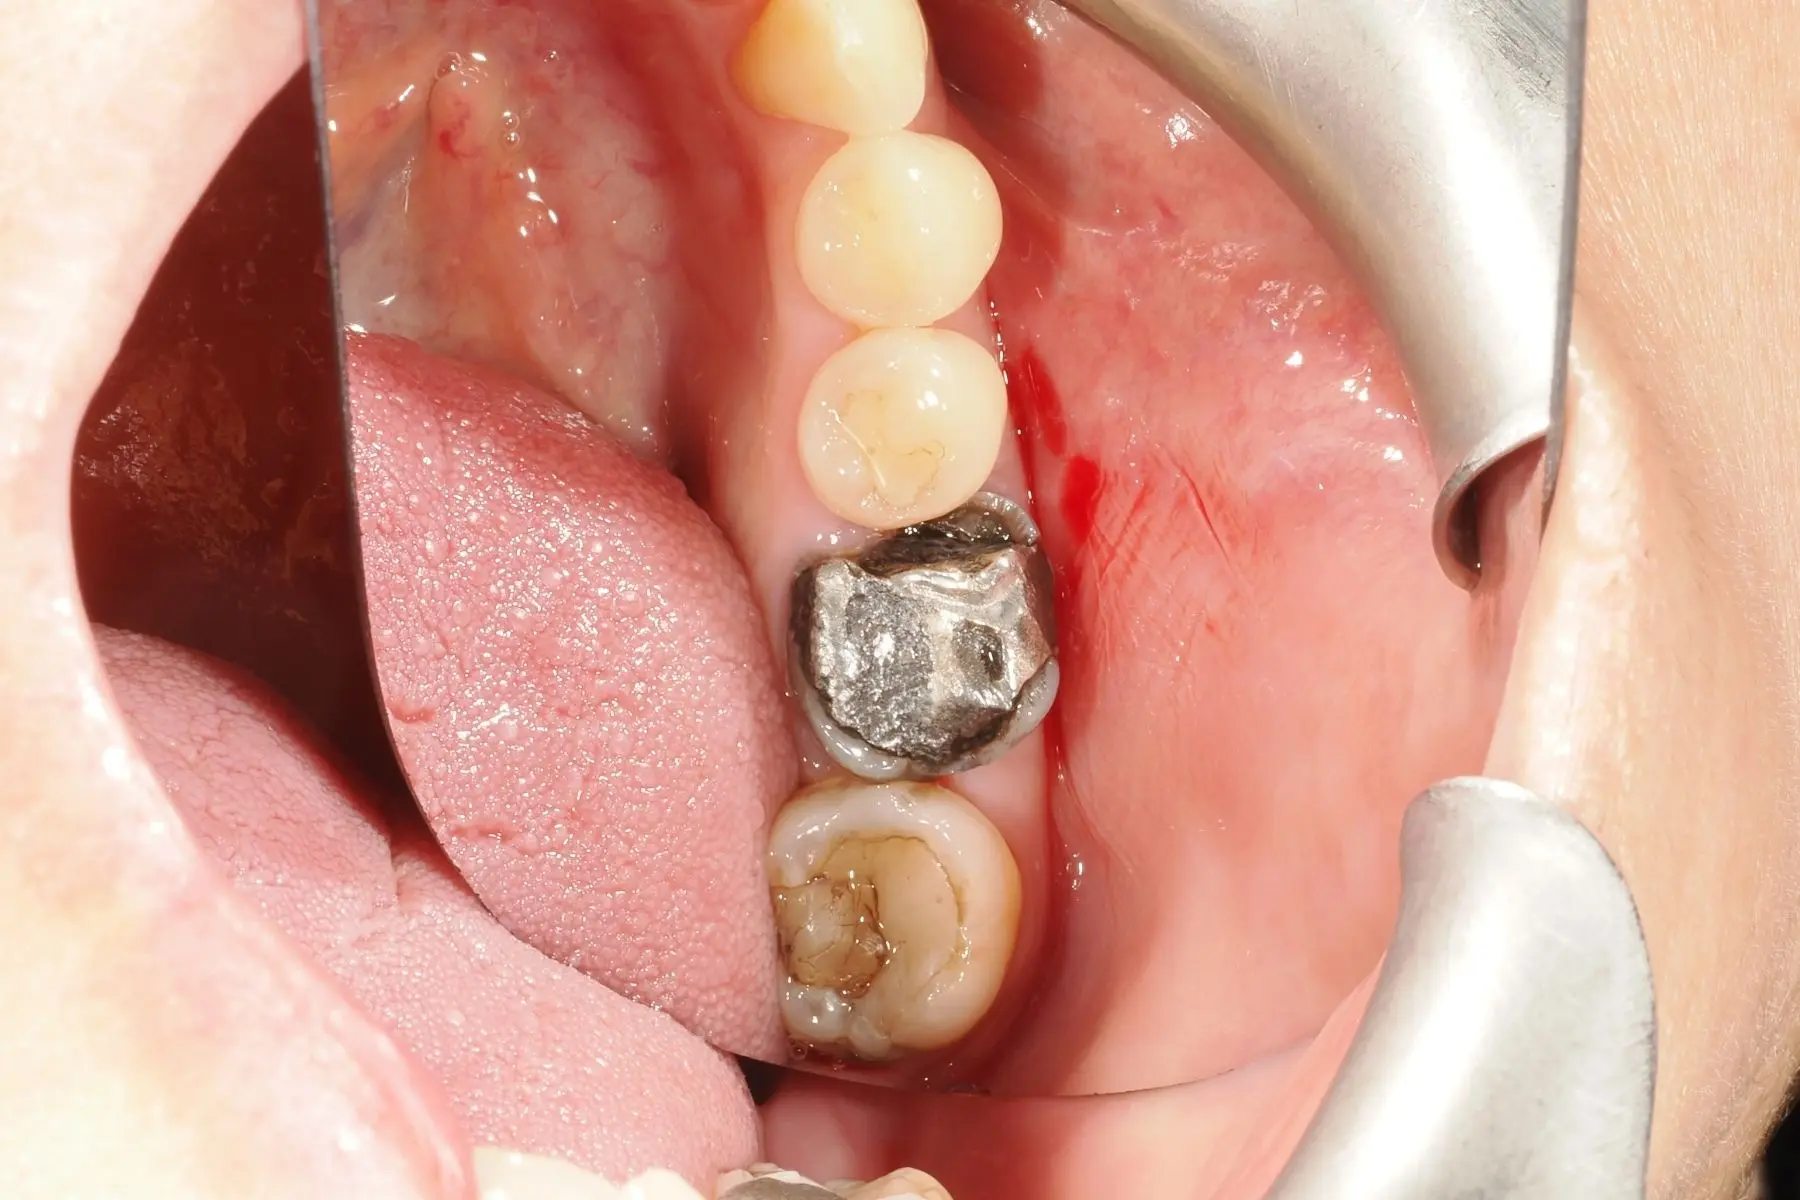

• 術前 33

術後 32

3D齒雕

主治醫師

• 楊明憲

治療時間

約4個月

主訴

洗牙檢查時,醫師發現口腔狀況不佳